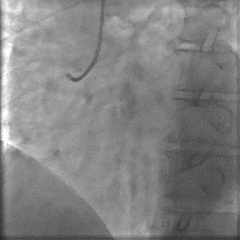

◾ 1个月后行择期PCI:

择期处理后侧支,并应用冠脉功能学全面评估解决方案(IMR/FFR等)进行左前降支IMR等的复查,测得LAD IMR 32(+),FFR 0.86,提示LAD仍存在CMD,但IMR值较前下降。

冠脉功能学全面评估:

▶ LAD IMR 32(+),FFR 0.86。